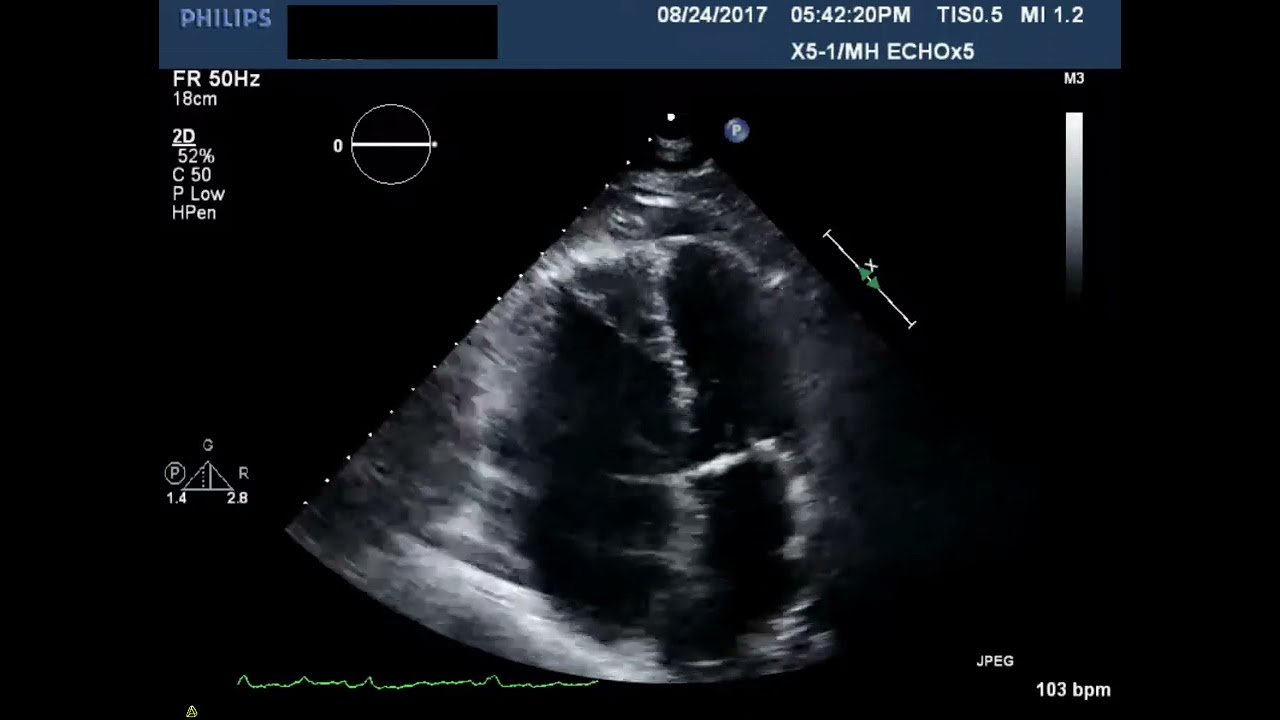

LV noncompaction CM

What is seen in this 2D image?